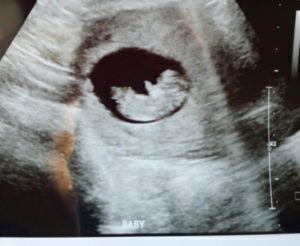

tubal-clip-reversal-baby-number-2-one-the-wayReversal baby Taylor #2!! Baby is growing right on schedule! Everything looks great! Heart rate 170.

This wouldnt be possible if it wasnt for Dr. Monteith and his crew!